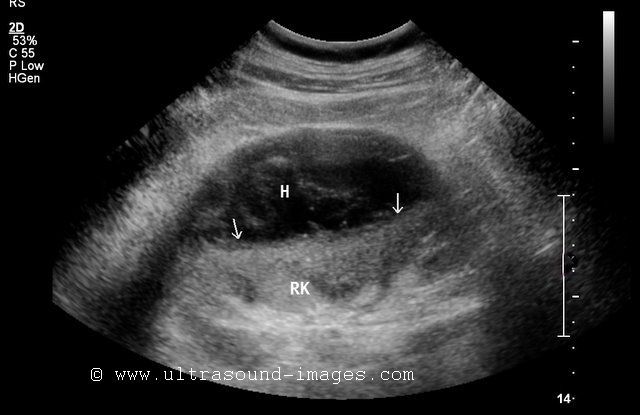

This patient, an adult female underwent routine sonography of the abdomen. Ultrasound images of the kidneys reveal multiple indentations (short arrows) of the renal cortex, with no evidence of fibrotic tissue (would be seen as hyperechoic bands). There is no evidence of thinning of the renal cortex or deformity of the pelvicalyces (ruling out chronic pyelonephritis). These ultrasound images show typical appearance of renal fetal lobulation. Fetal lobulation is a common finding and is a normal variant of the kidneys. It is caused by the persistence, into adult life, of the lobulation of the kidneys seen normally during fetal stage.